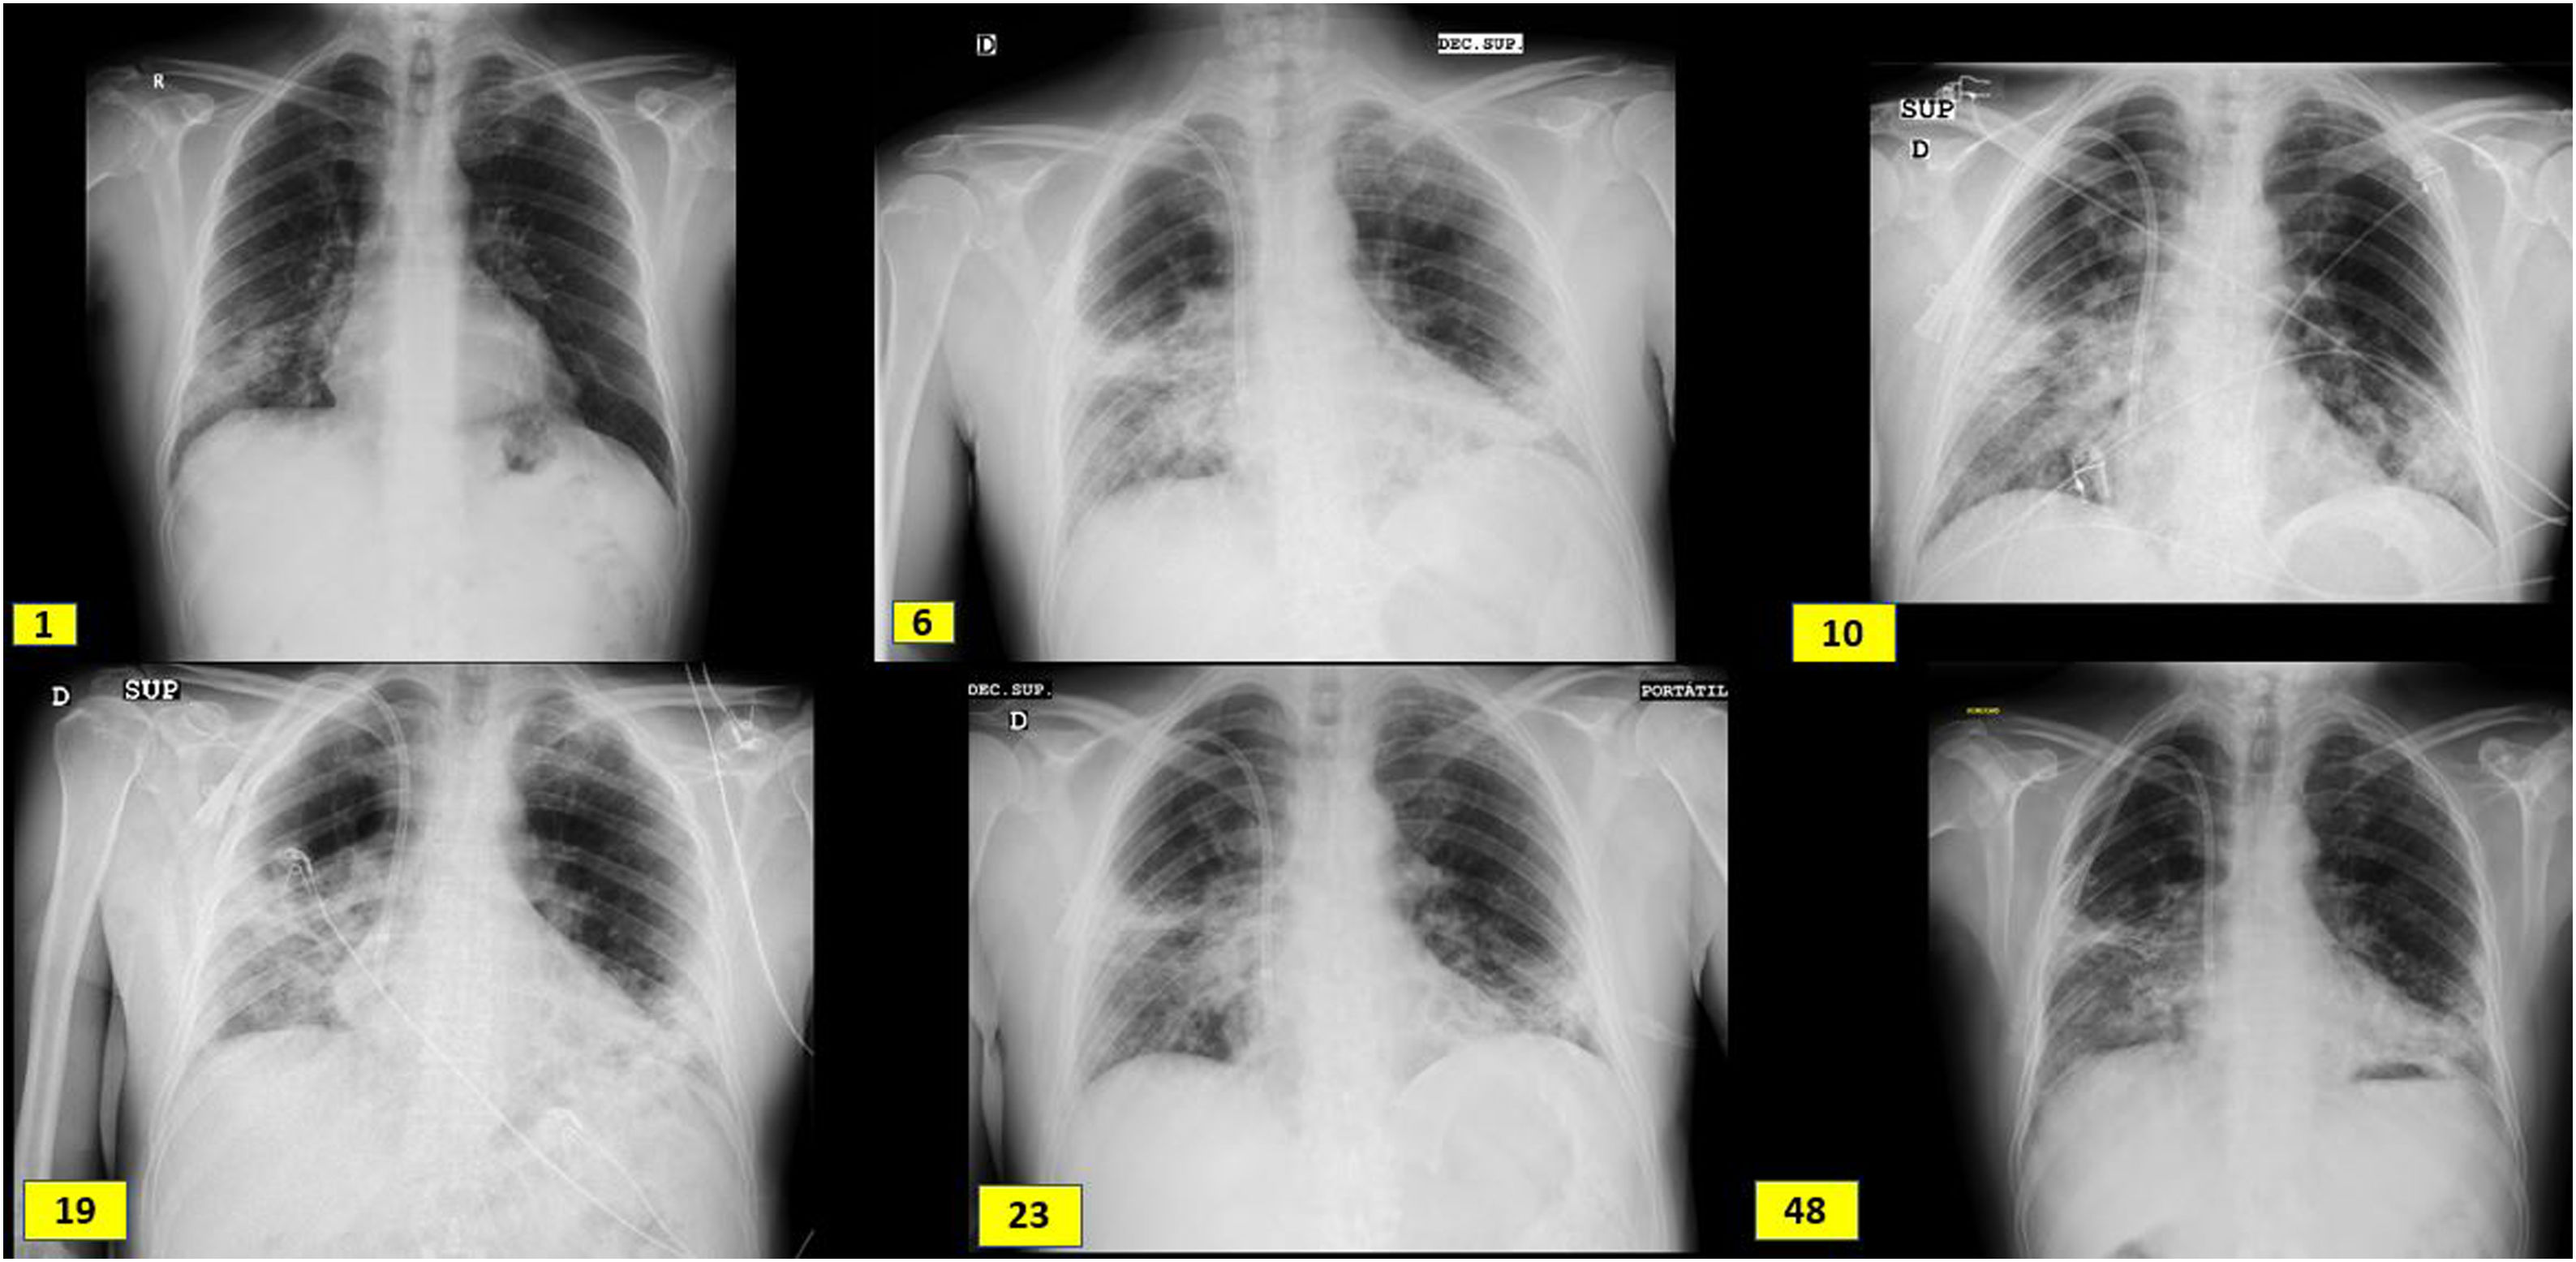

Evolución radiológica coincidiendo con el ingreso (día 1), bolos de metilprednisolona (día 6), biopsia renal (día 10), inicio de tocilizumab (día 19), inicio de rituximab (día 23) y alta del hospital (día 48). Presenta engrosamientos reticulares periféricos subpleurales de campos medios, base derecha, y língula y opacidades alveolares intersticiales en campos medios e inferiores de pulmón derecho y campos inferiores del pulmón izquierdo.

ExposiciónVarón de 60 años de origen ecuatoriano que ingresa en agosto 2020 por disnea de unos días de evolución, sin ningún otro síntoma referido. A su llegada se muestra normotenso y afebril con saturación basal de oxígeno mayor del 94%, pero taquipneico a 16 respiraciones por minuto. Se realiza RT-PCR frente al SARS-CoV-2 en exudado faríngeo con resultado positivo. En el estudio de laboratorio se identifican parámetros habituales de infección COVID, siendo llamativa la afectación renal: Creatinina en plasma 3,94mg/dl, FGe (CKD-EPI): 16ml/min/1,73m2, microhematuria e indicios de proteínas (tabla 1). Radiografía de tórax con neumonía bilateral intersticial (imagen 1). El paciente trabajaba como pintor en la construcción, no tenía hábitos tóxicos ni contacto con animales, y era hipertenso de larga duración.